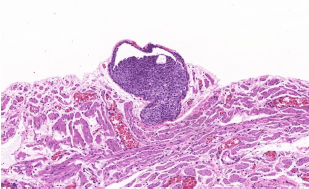

Homem, 25 anos, com nódulo bem delimitado de 1 cm, sem topografia especificada. Recebido fuso de pele com lesão nodular central. Observe a figura abaixo. Assinale a alternativa que apresenta o diagnóstico.